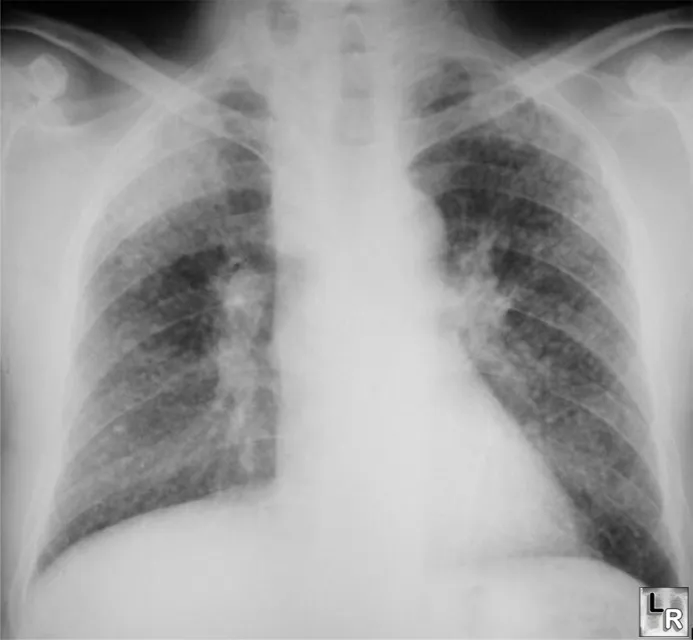

- Radiology:

- Small, rounded opacities, predominantly upper lung zones. 📌 Mnemonic for upper lobe: "STAB C" (Silicosis, TB, Ankylosing Spondylitis, Berylliosis, CWP).

⭐ Silicosis shows 'egg-shell' calcification of hilar lymph nodes and predominantly affects upper lung zones.

- Silicosis: Upper lobe opacities, eggshell calcification of hilar nodes, increased TB risk.